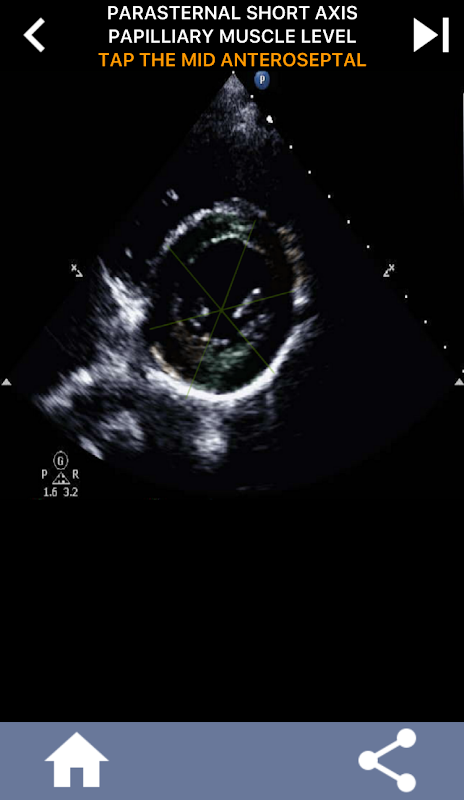

رویکرد بصری مبتنی بر آزمون برای یادگیری بخشهای قلب AHA: اکوکاردیوگرافی

درک بخش های قلب AHA (انجمن قلب آمریکا) برای یک متخصص سونوگرافی قلب برای برقراری ارتباط موثر با متخصص قلب که گزارش را می نویسد بسیار مهم است. با دانستن نواحی آناتومیکی خاص و بخشهای مربوط به آنها، سونوگرافیست میتواند هر گونه ناهنجاری یا یافتهای را بهطور دقیق توصیف کرده و با آن ارتباط برقرار کند و از ارتباط واضح و مختصر بین هر دو متخصص اطمینان حاصل کند.

این درک به ویژه زمانی بسیار مهم می شود که متخصص قلب به دنبال تعیین محل دقیق یک مشکل باشد یا زمانی که پزشک در حال خدمت مشکلی را در یک منطقه خاص شناسایی می کند و سونوگرافیست را وادار می کند تا قسمت مربوطه را به طور دقیق نمایش دهد، مانند دیواره میانی تحتانی. بنابراین، داشتن درک جامع از بخش های قلب AHA مجموعه مهارت های ضروری است.

این برنامه دانش شما را با استفاده از تصاویر پژواک واقعی آزمایش میکند، که اغلب آنها را بهترین روش تدریس میدانم.